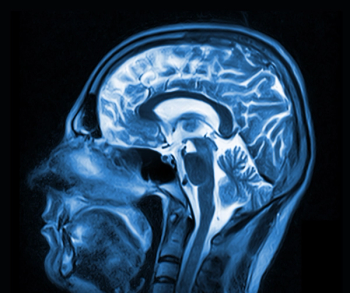

Researchers found that a higher waist-to-hip ratio in midlife was associated with higher mean diffusivity in 26 percent of total white matter tracts in the cingulum as well as the superior and inferior longitudinal fasciculus.